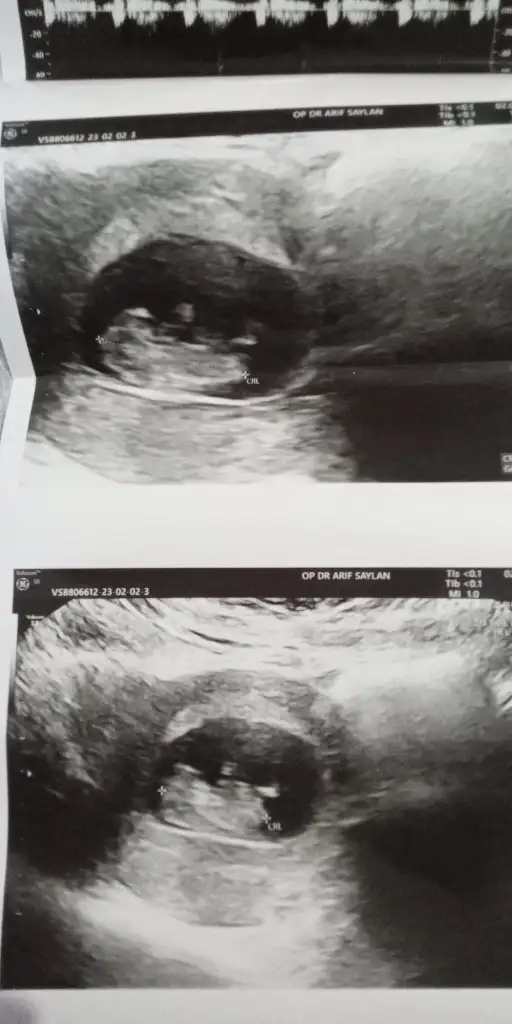

Rica etsem banada bakarmisiniz çok merak ediyorum 🥰☺️❤️

Eklentiler

• Screenshot_20230204-002246.webp

Screenshot_20230204-002246.webp

13,7 KB · Görüntüleme: 92

• IMG_20230202_182730_387.webp

IMG_20230202_182730_387.webp

23,3 KB · Görüntüleme: 67

• IMG_20230202_182706_519.webp

IMG_20230202_182706_519.webp

25 KB · Görüntüleme: 77

• IMG_20230202_182701_639.webp

IMG_20230202_182701_639.webp

27 KB · Görüntüleme: 83